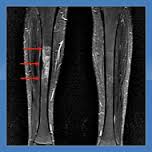

An MRI is the best tool for diagnosing stress fractures. X-rays are likely to result in false negatives upon initial presentation, especially in the early stages of stress fractures and in some cases may not reveal an existing stress fracture at any time.